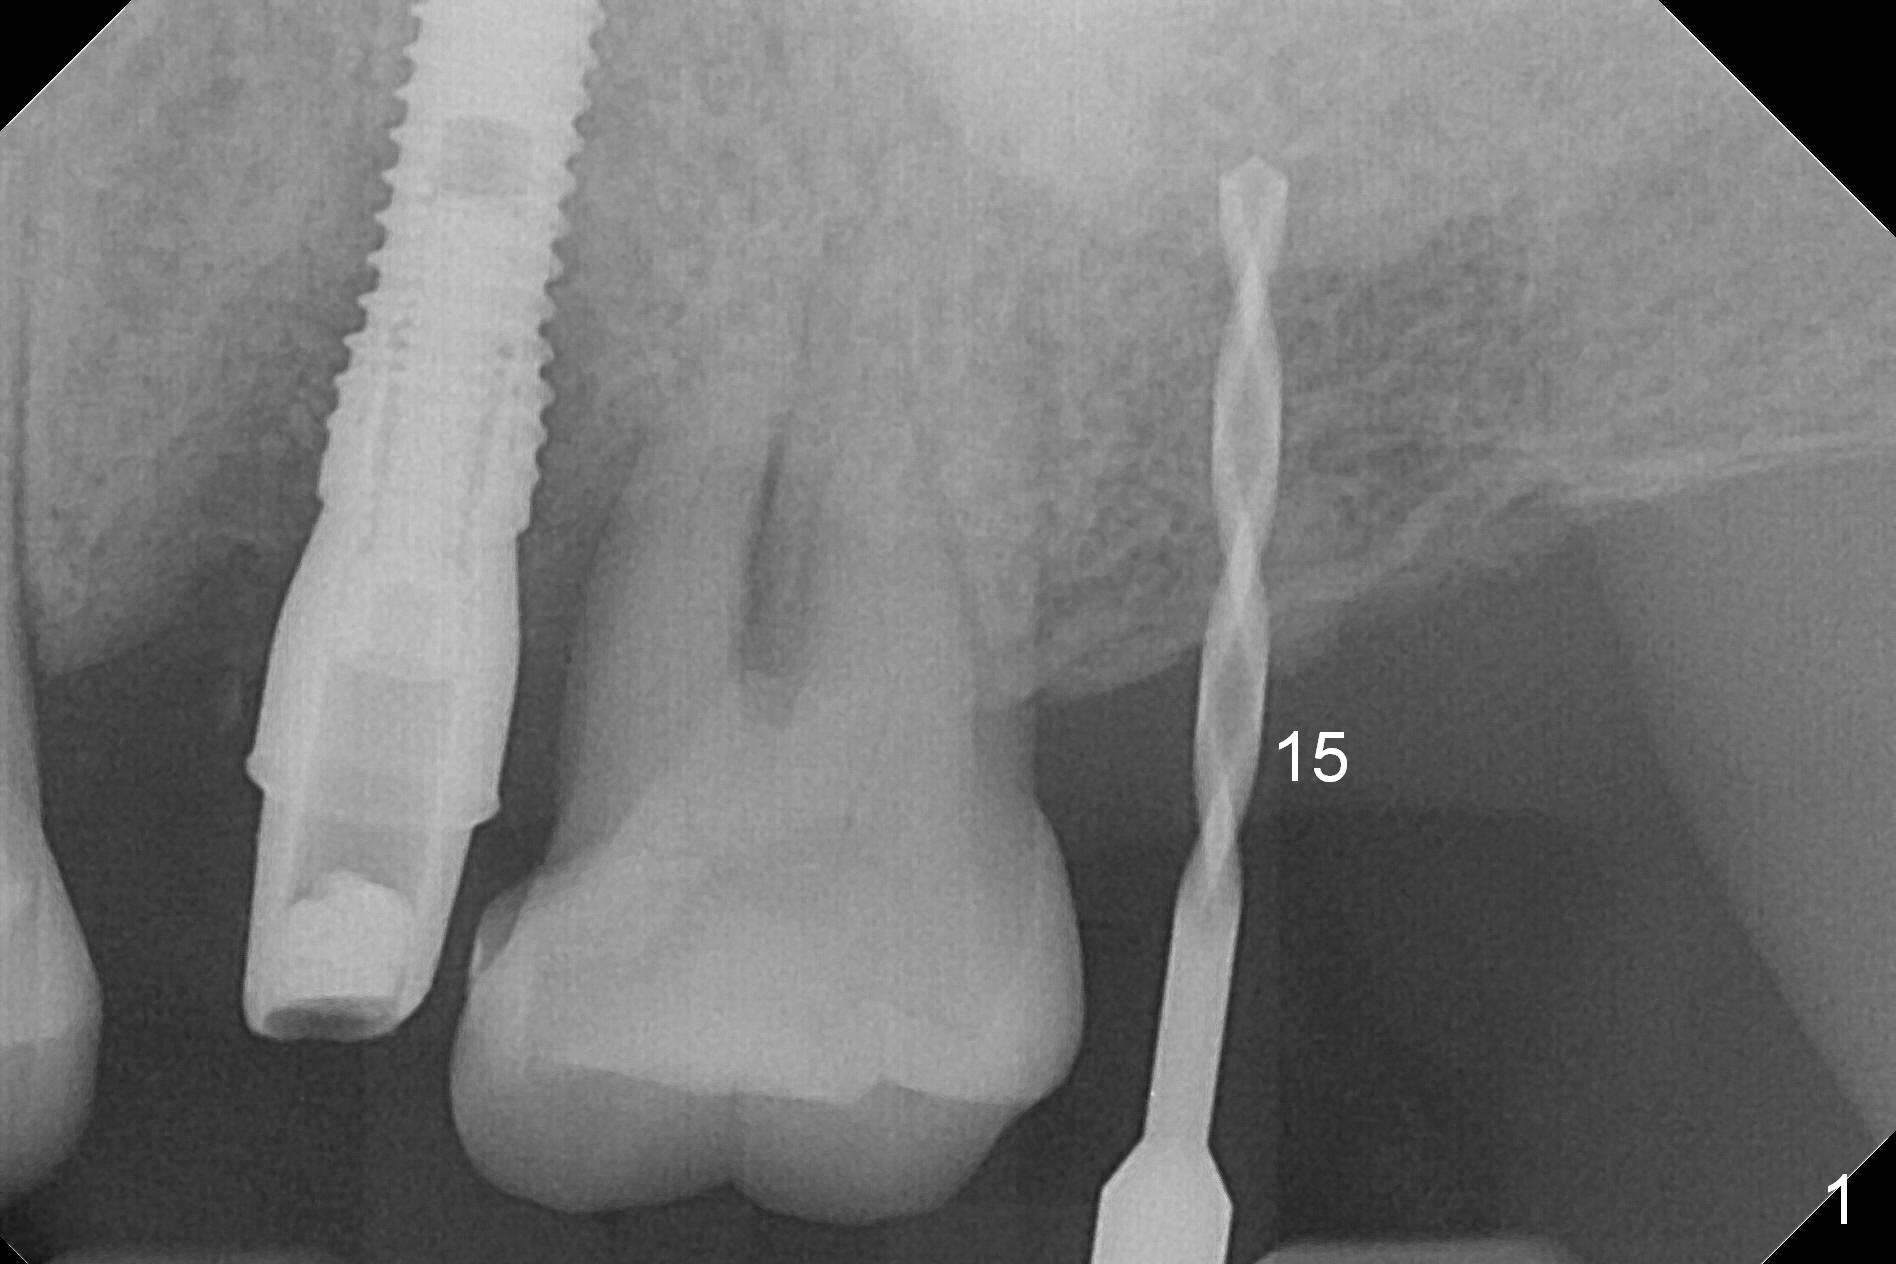

A 1.2 mm initial drill is used to start osteotomy at the site of #15 (Fig.1). After moving the osteotomy distally (with Lindamann bur), the osteotomy is enlarged by DIO Bone Expanders until 2.4/3.7 mm for 18 mm (gingival level) (Fig.2). Following the expander 3.0/4.4 mm, a 5x13 mm UF implant is placed supracrestal (Fig.3,4). After deepening the osteotomy with 3.8 mm drill for 3 mm, the implant is placed deeper by ~ 2 mm (Fig.5 arrow). Since the tooth #18 is supraerupted, a healing abutment (5.5x12(3) mm) is placed (Fig.6: H); the gingiva adapts to the abutment well. Suture is not necessary. The bone remains stable 2 and 4.5 months postop (Fig.7,8). Impression is taken. A crown is delivered nearly 6 months postop (08/07/2017). While there is minimal bone loss at #13 and 15 three years and 4 months post cementation, the tooth #14 and 18 are mobile (Fig.13,14, #13).